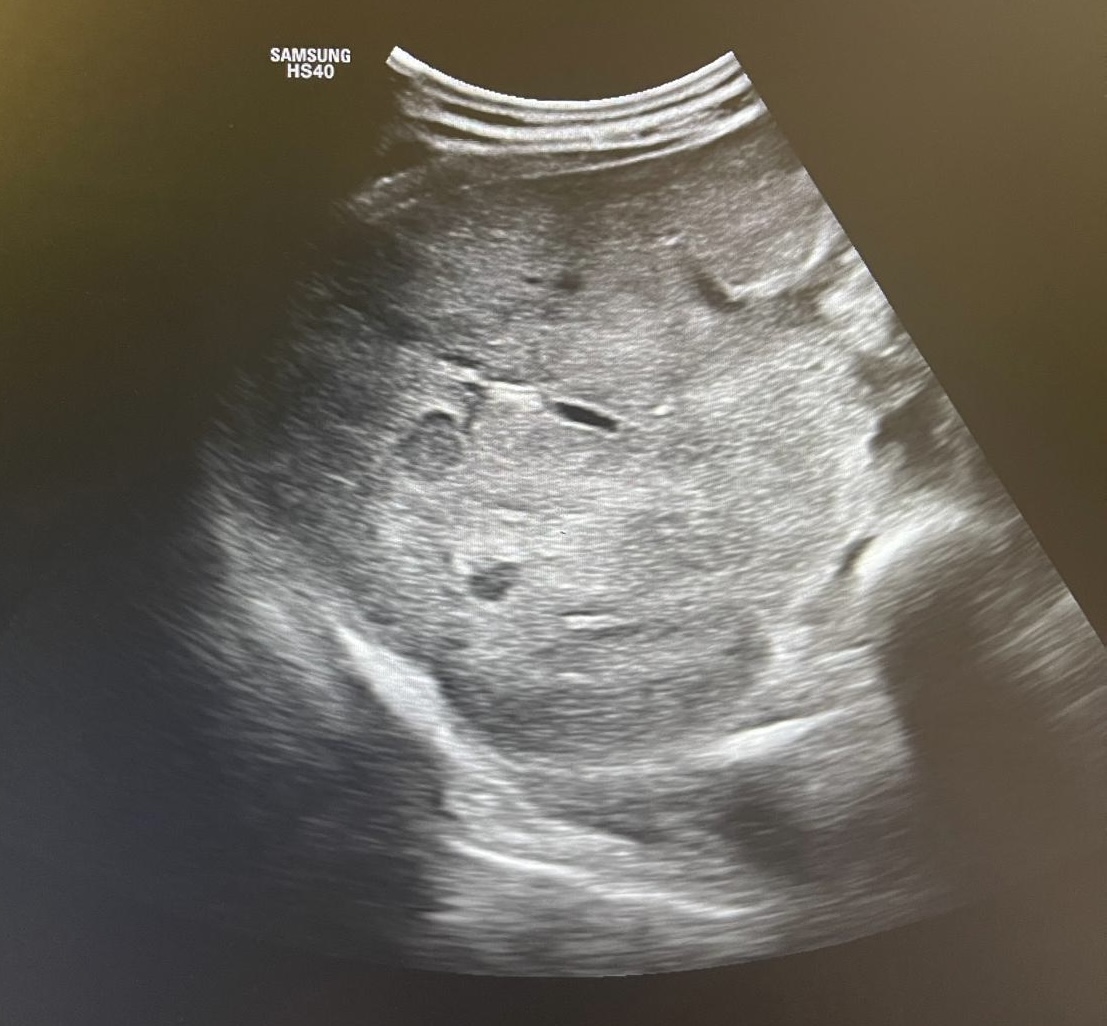

Hallazgos ecográficos

En la ecoscopia se observan múltiples nódulos hipoecoicos en el parénquima hepático sugestivos de afectación metastásica. Se solicita ecografía reglada preferente, confirmándose el hallazgo de nódulos hipoecogénicos de predominio en el lóbulo izquierdo hepático.